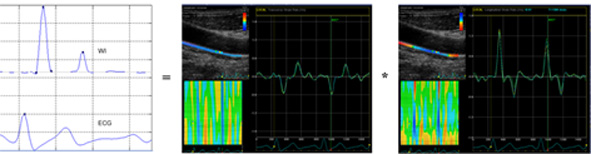

En schematisk bild av hur wave intensity beräknas med WIWA-metoden: WI = - deformationshastighet (radiellt) * deformationshastighet (longitudinellt).

Inom wave intensity analysis definieras arteriella vågor som sekventiella, infinitesimala förändringar av blodtryck och blodhastighet. Vår nya metod, wave intensity wall analysis (WIWA), approximerar dessa förändringar genom mätningar av deformationshastighet i radiell och longitudinell riktning; tryckkomponenten (dP/dt) approximeras med deformationshastighet i radiell riktning och blodhastighetskomponenten (dU/dt) med deformationshastighet i longitudinell riktning. Positiv deformation motsvarar stretching och negativ deformation kompression i förhållande till den ursprungliga längden och således är den radiella komponenten teckenändrad i WIWA-beräkningar.